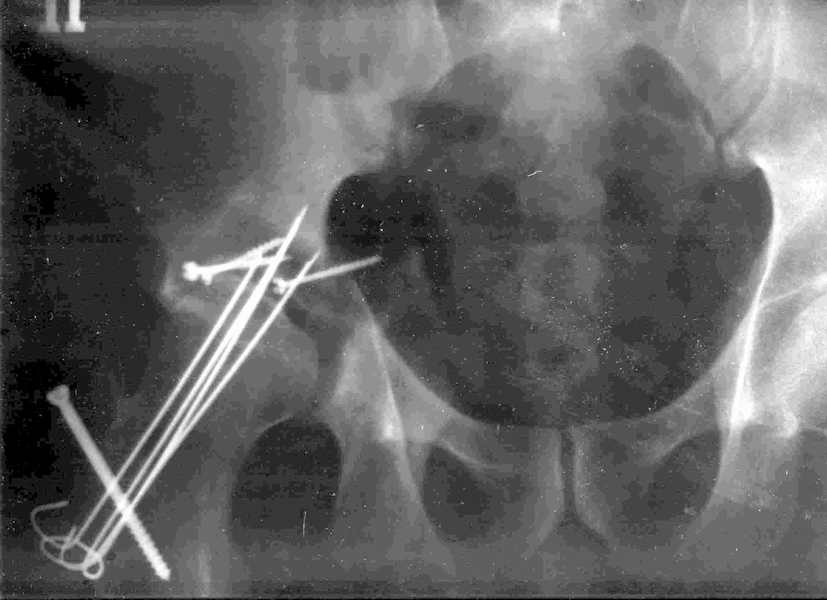

Xray1

Xray2

Высылаю прямой обзорный и косой подвзошный снимки, косой запирательный неудовлетворительного качества.